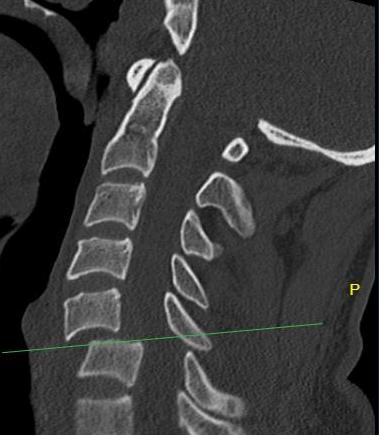

Unilateral facet joint dislocation on CT